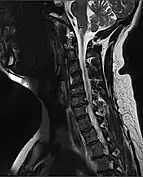

| MRI of a fractured and dislocated cervical vertebra (C4) in the neck that is compressing the spinal cord | |